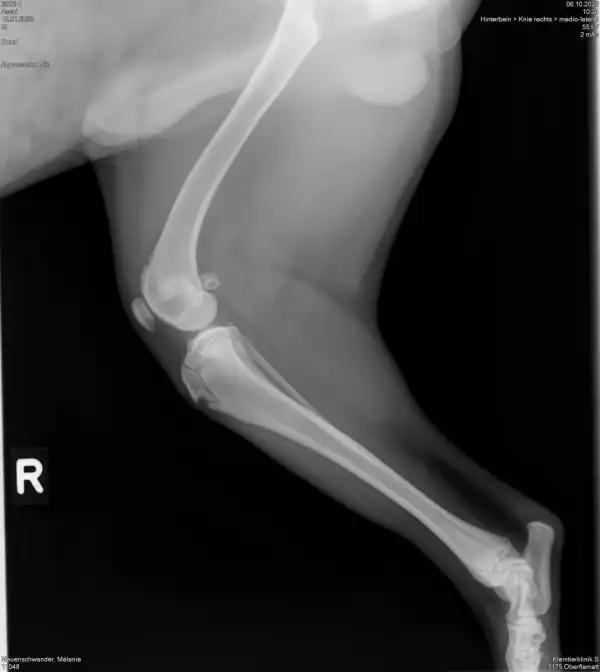

Aschi muss an beiden Knien Operiert werden.

Aschi hat in den elf Monaten seines Lebens noch nicht viel Freude gehabt. Mit gerade mal sieben Wochen hatte er einen schweren Unfall. Seither versuchen wir alles, dass Aschi ein normales Schmerzfreies Hundeleben leben kann. Leider steigen die Kosten immer höher und die teuren Knieoperationen stehen noch bevor. Da wir ihn direkt nach dem Unfall abgeholt haben und zum Notfall Tierarzt mussten, konnten wir keine Versicherung abschliessen.